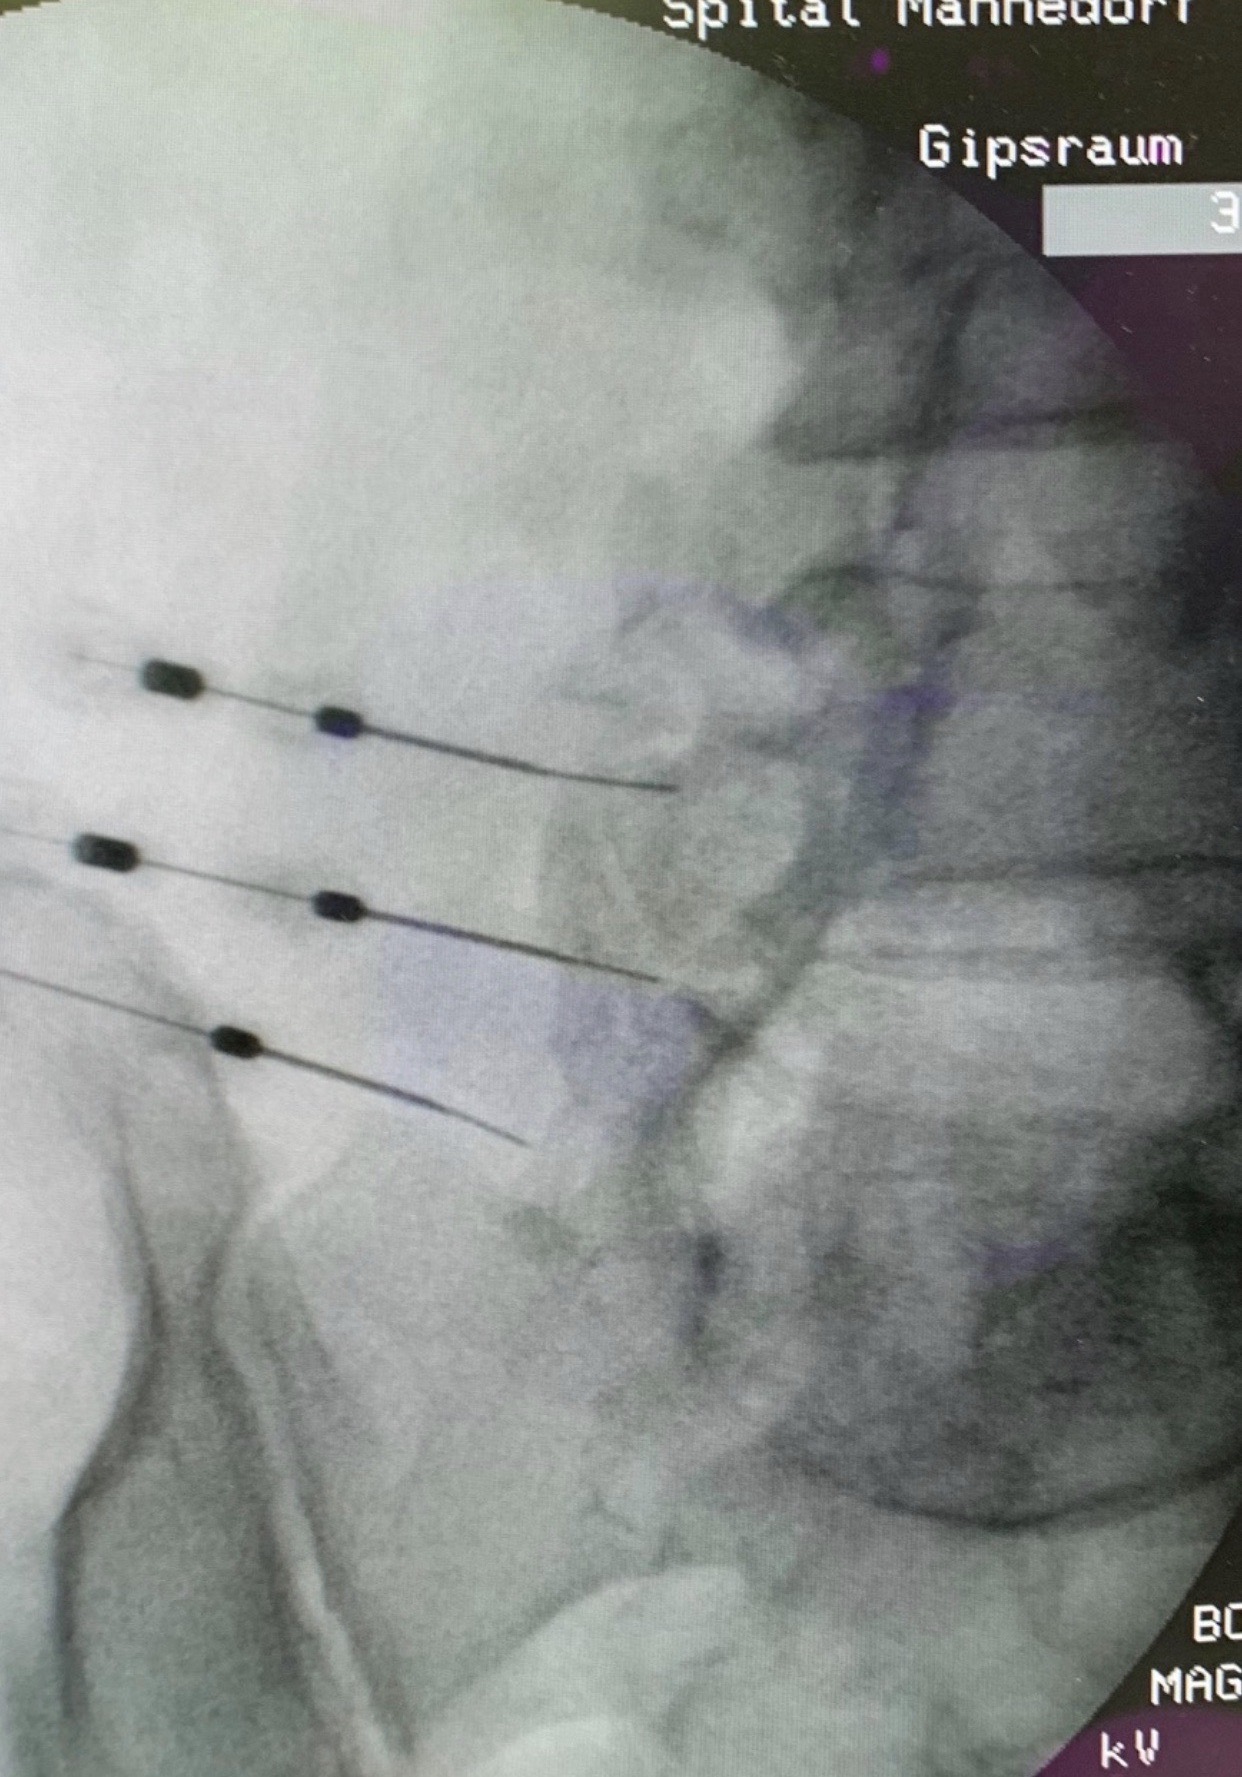

Interventionelle Wirbelsäuletherapie / PRT

Geeignet für Bandscheibenvorfälle, Spinalstenose und Verschleiss der kleinen Wirbelgelenke – ohne Operation. Durch die Einengung und den Druck auf Nervenwurzeln und Rückenmark werden Symptome wie Rücken- und Nackenschmerz, häufig auch mit Ausstrahlung in Arme oder Beine, verursacht. Begleitend treten oft Gefühlsstörungen, Muskelkrämpfe, lahme Beine, Schwindel oder Kopfschmerz auf.

Bei der interventionellen Wirbelsäulentherapie wird mit Hilfe der Bildgebung eine Injektionsnadel punktgenau platziert. Der Therapieeffekt beruht auf der entzündungshemmenden und abschwellenden Wirkung der injizierten Medikamente. Nerven schwellen ab und gewinnen mehr Platz. Ein Zusatzeffekt ist die vorübergehende Betäubung der Nerven und somit eine Schmerzlinderung.